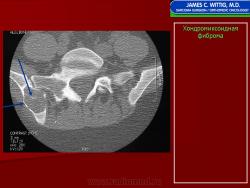

Хондромиксоидная фиброма

Хондромиксоидная фиброма

Хондромиксоидная фиброма

Хондромиксоидная фиброма

Хондромиксоидная фиброма

Хондромиксоидная фиброма

Рентгенологическая картина. Хондромиксоидная фиброма длинных трубчатых костей в типичных случаях представлена метафизарным или метадиафизарным, эксцентричным, четко очерченным, овальным очагом разряжения костной ткани с истон чением и вздутием коркового слоя с одной стороны.